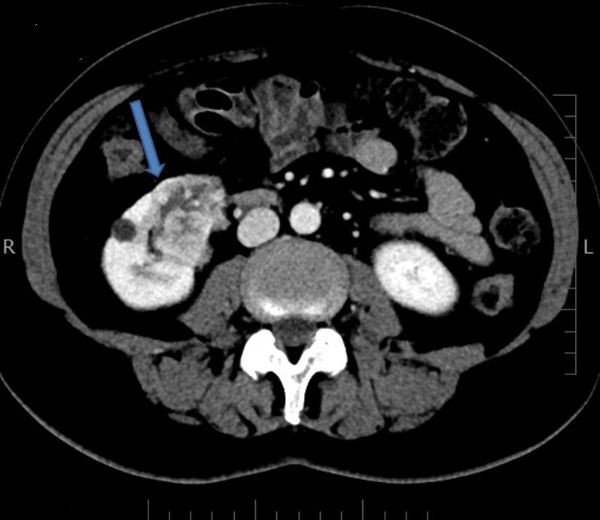

Muž 58 let – světlobuněčný karcinom

Na vyšetření přišel 58letý Jan Vokřálek, který byl předtím vyšetřen praktickým lékařem (PL). Pacient již 3 dny trpí trvajícím otokem pravé dolní končetiny, praktický lékař mu zjistil suspektní tromboflebitidu. Dále trpí dyspeptickým syndromem. Lumbalgií netrpí, hematurii neguje.